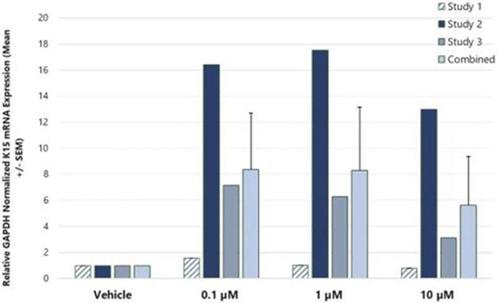

In addition to relief of symptoms, inflammation, pain, and others, we believe INM-755 may impact the underlying disease by enhancing skin integrity in a subset of EB patients. We have completed more than 30 preclinical pharmacology and toxicology studies to investigate the effects of CBN. Several of these nonclinical studies explored the effect on important symptoms such as pain and inflammation. In in vitro pharmacology studies, CBN demonstrated activity in reducing markers of inflammation. CBN upregulated expression of a type of keratin called keratin 15, or “K15”, which might lead to skin strengthening and reduced blister formation in EB simplex, or “EBS”, patients with mutations in another keratin called keratin 14, or “K14”. The anti-inflammatory activity of CBN may be beneficial in healing chronic wounds caused by prolonged inflammation. Following a review of our toxicology studies, the Netherlands National Competent Authority and Ethics Committee approved the initiation of a Phase I clinical study in healthy volunteers. We have safety data with INM-755 cream in 22 healthy adult volunteers from our first Phase I study (755-101-HV) in which subjects had the INM-755 cream applied to their upper backs daily for 14 days. An interim safety analysis of the first 16 subjects was reviewed by the Netherlands National Competent Authority and Ethics Committee and determined to be adequate to allow initiation of the second Phase I study testing INM-755 cream on small wounds. That second study has completed and we now have safety data for INM-755 cream applied to small open wounds daily for 14 days in 8 healthy adult volunteers.

In preclinical pharmacology studies, CBN demonstrated activity as an anti-inflammatory and antinociceptive agent. CBN upregulated expression of keratin 15 (K15), which might lead to skin strengthening and reduced blister formation in EBS patients with keratin 14 (K14) mutations. At the cream concentrations chosen for clinical development, it does not appear to impede wound healing of partial-thickness wounds. Its anti-inflammatory activity may be beneficial in healing chronic wounds caused by prolonged inflammation.